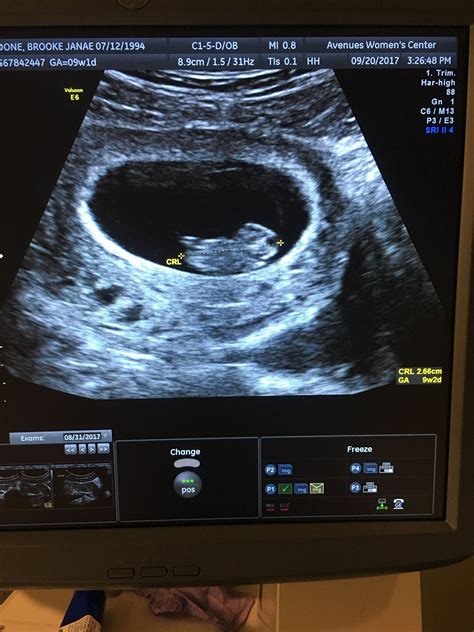

At 9 weeks, the fetus is still very small, but several key features can be visualized:

• Gestational Sac: This is the fluid-filled structure that contains the embryo.

• Embryo: The embryo itself, which is about the size of a grape, can be seen with a distinct head and body.

• Fetal Heartbeat: The heartbeat is usually visible and audible, providing reassurance of the fetus’s health.

• Crown-Rump Length (CRL): This is the measurement from the top of the head to the bottom of the buttocks. At 9 weeks, the CRL is typically around 21-27 mm.

• Gestational Age: The ultrasound can help confirm the gestational age, which is crucial for monitoring the pregnancy and planning future care.